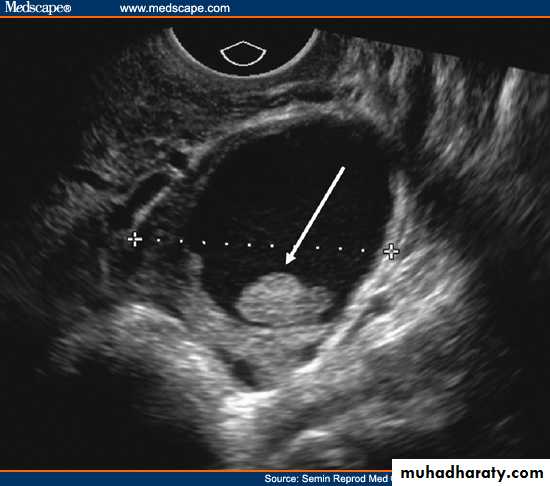

PERSISTENT ANOVULATORY FOLLICLE

Failure of ovulation and development of “cystic” follicle. The follicle typically grows larger than the mean preovulatory follicle diameter of 23 mm, thin atretic follicle walls are observed and small flecks of particulate matter are frequently seen in the lumen or aggregated at the side of the structure.